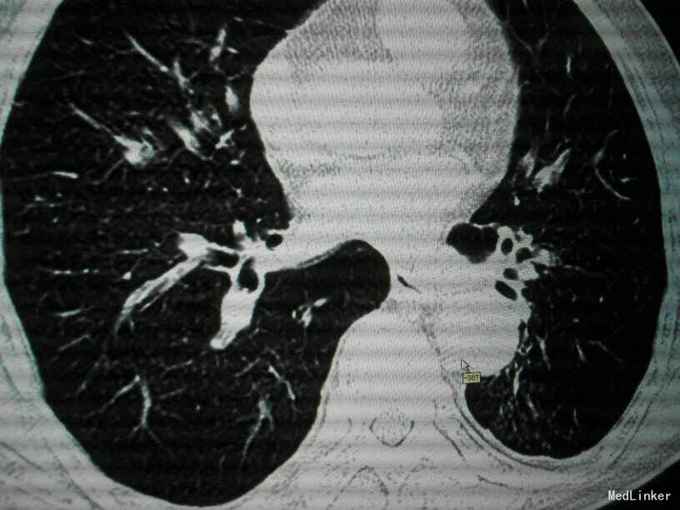

查体:唇指发绀,桶状胸,肋间隙增宽,双肺叩诊呈过清音,双肺呼吸音粗,可闻及散在干湿性啰音,未闻及明显湿性罗音,呼气延长,心腹阴性,双下肢轻度水肿。 辅助检查:入院后血气分析 PH 7.41 PCO2 43mmHg,PO2 73mmHg,BE 2.7mmol/L SO2:96%;心电图:室性早搏;胸片:符合慢支合并双肺炎症;肺CT示1.两肺多发支气管扩张并感染2.两肺间质纤维化,两侧胸膜增厚;心脏彩超:肺动脉压增高,肺动脉略宽;痰培养:肺炎克雷伯杆菌亚种;

诊断:慢阻肺急性发作;支气管扩张并感染;肺间质纤维化;慢性肺心病 治疗经过:抗炎:哌拉西林他唑巴坦;化痰:羧甲司坦口服液+盐酸氨溴索针;解痉平喘:多索茶碱,复方异丙托溴铵雾化溶液+布地奈德雾化混悬剂,雾化吸入;扩冠、减轻心脏负荷:硝酸甘油针;利尿:拖拉塞米针;3日后停硝酸甘油,改单硝酸异山梨酯缓释片口服,后患者出现胸闷、胸痛、气短症状加重,请心内科会诊后,给予呋塞米20㎎,隔日1次口服;螺内酯片20㎎,1日1次;替米沙坦片40㎎ 1日1次;美托洛尔6.25㎎;氯化钾缓释片 0.5g,1日2次;并给予抗血小板聚集、调脂、稳定斑块等治疗;治疗10天后,患者受凉后出现畏寒、发热,侧体温38.1℃,停哌拉西林他唑巴坦,改为盐酸莫西沙星针0.4g,1日1次,其余治疗同前;治疗3天后患者体温恢复正常,偶有咳嗽,咳少量白色黏痰,症状好转,出院。